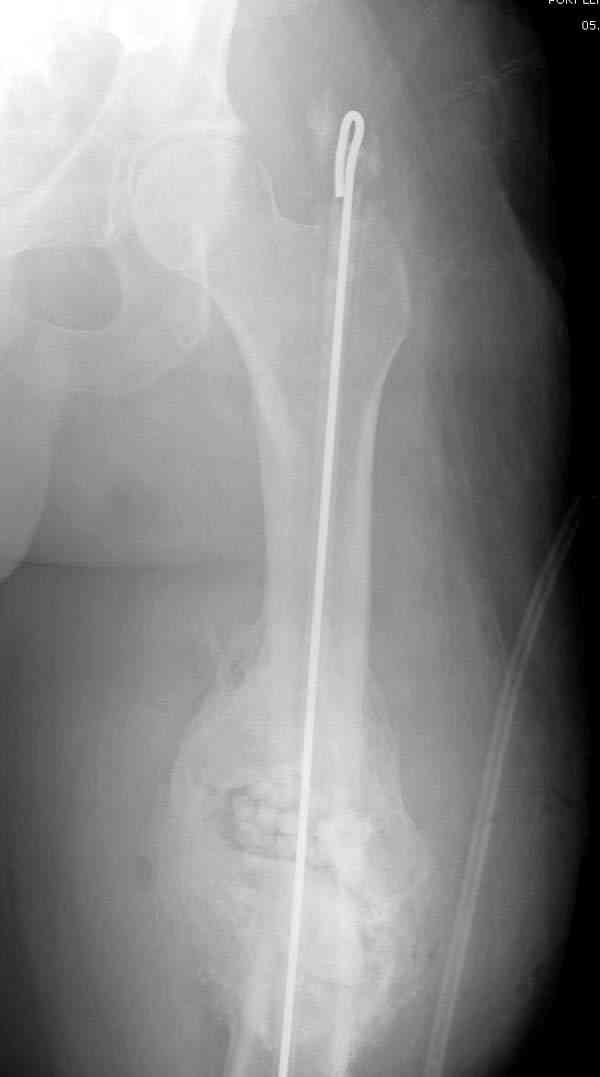

Мы бы начали с санации очага и заполнения полости антибиотическими бусами. Для создания устойчивой конечности и для профилактики стрессовых переломов, костный канал заполняем “custom made antibiotic nail”, который готовится "экстемпоре"

После определения длины канала берется 3мм длинная проволока, обычно "long guided wire" от интрамедуллярного набора, концы загибаются, ее

вставляют в трубку, трубку заполняют цементом с антибиотиком.

Канал до вставления гвоздя рассверливается на пару мм, а взятая большего диаметра внутренная арматура обычно удерживает конечность, даже в некоторых случаях, при небольшом дефекте, и вес больного.

старый снтибиотический гвоздь

ренгенограмма инфицированного бедра со старым

антибиотическим гвоздем